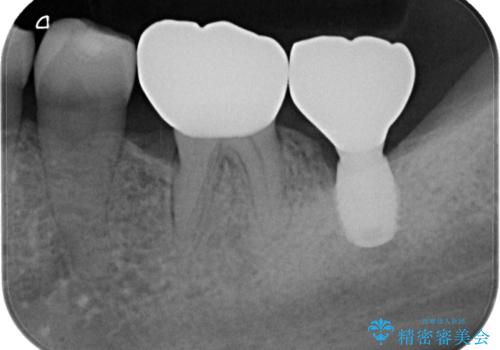

- 左下奥のクラウンに違和感を感じるとのことで来院された患者様です。

最後方歯は歯槽骨よりも深い部分にまでむし歯が及んでおり、患者様と相談の上、インプラントによる補綴治療を行うこととしました。

根尖部の病変が小さいことから抜歯即時埋入が選択されるところですが、抜歯窩洞が大きくなることと、窩洞直下に神経や血管が走行していることから、抜歯してから2,3ヶ月待機してから埋入することとしました。

骨の高さが不十分であったため、インプラント強度を維持しながらも高さの小さいインプランを使用しました。